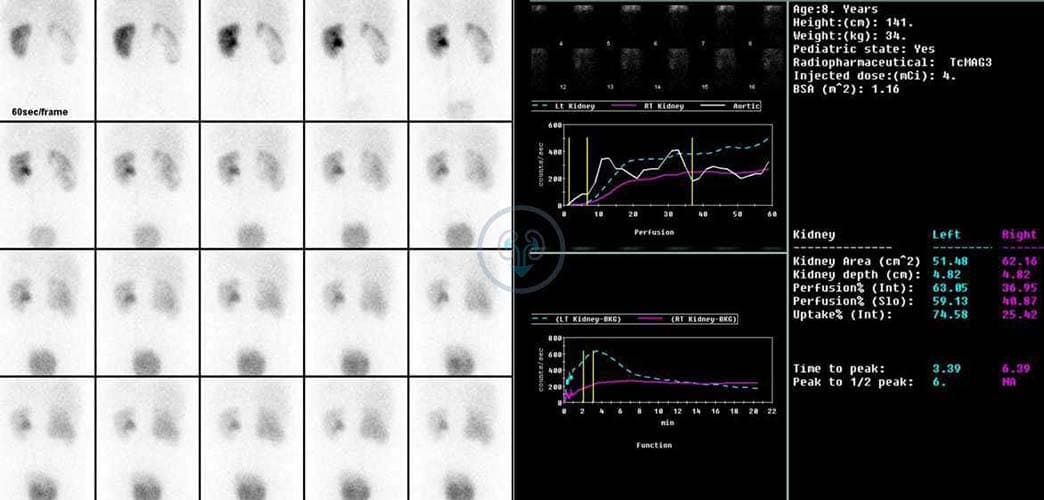

Радиоизотопная реносцинтиграфия дает информацию о функциональном состоянии органа, позволяет оценить тяжесть изменений, вызванных обструкцией. При нарушении функции мочки отмечается замедление выведения изотопа MAG3 (меркаптоацетилглицерин). При необходимости вводят диуретический препарат для определения оттока мочи при повышенной водной нагрузке и дифференциальной диагностики наличия препятствия в зоне ЛМС.

В качестве дополнительных методов диагностики применяют внутривенную урографию, цистографию, радиоизотопное изучение почек.